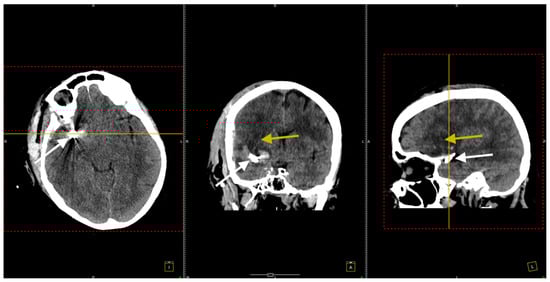

Postoperative cerebral CT scans showed a right frontotemporal hypodensity suggestive of sequelae of the ischemic stroke, correlating with her left-sided motor deficit (Figure 4).

Figure 4. Postoperative CT scan. All three sections, transversal (left image), coronal (middle image), and sagittal (right image), show clip placement (white arrows) and sequelae from the ischemic stroke. The yellow arrows indicate areas of hypodensity corresponding to ischemic stroke sequelae in the right frontotemporal region.

At her 3-month follow-up check, a repeat native cerebral CT scan was conducted (Figure 7).

Figure 7. The CT scan conducted 3 months after the surgical procedure. All three sections, transversal (left image), coronal (middle image), and sagittal (right image), confirmed the right frontotemporal hypodensity consistent with ischemic stroke (yellow arrows) and noted artifacts from the previously placed aneurysm clips (white arrows).